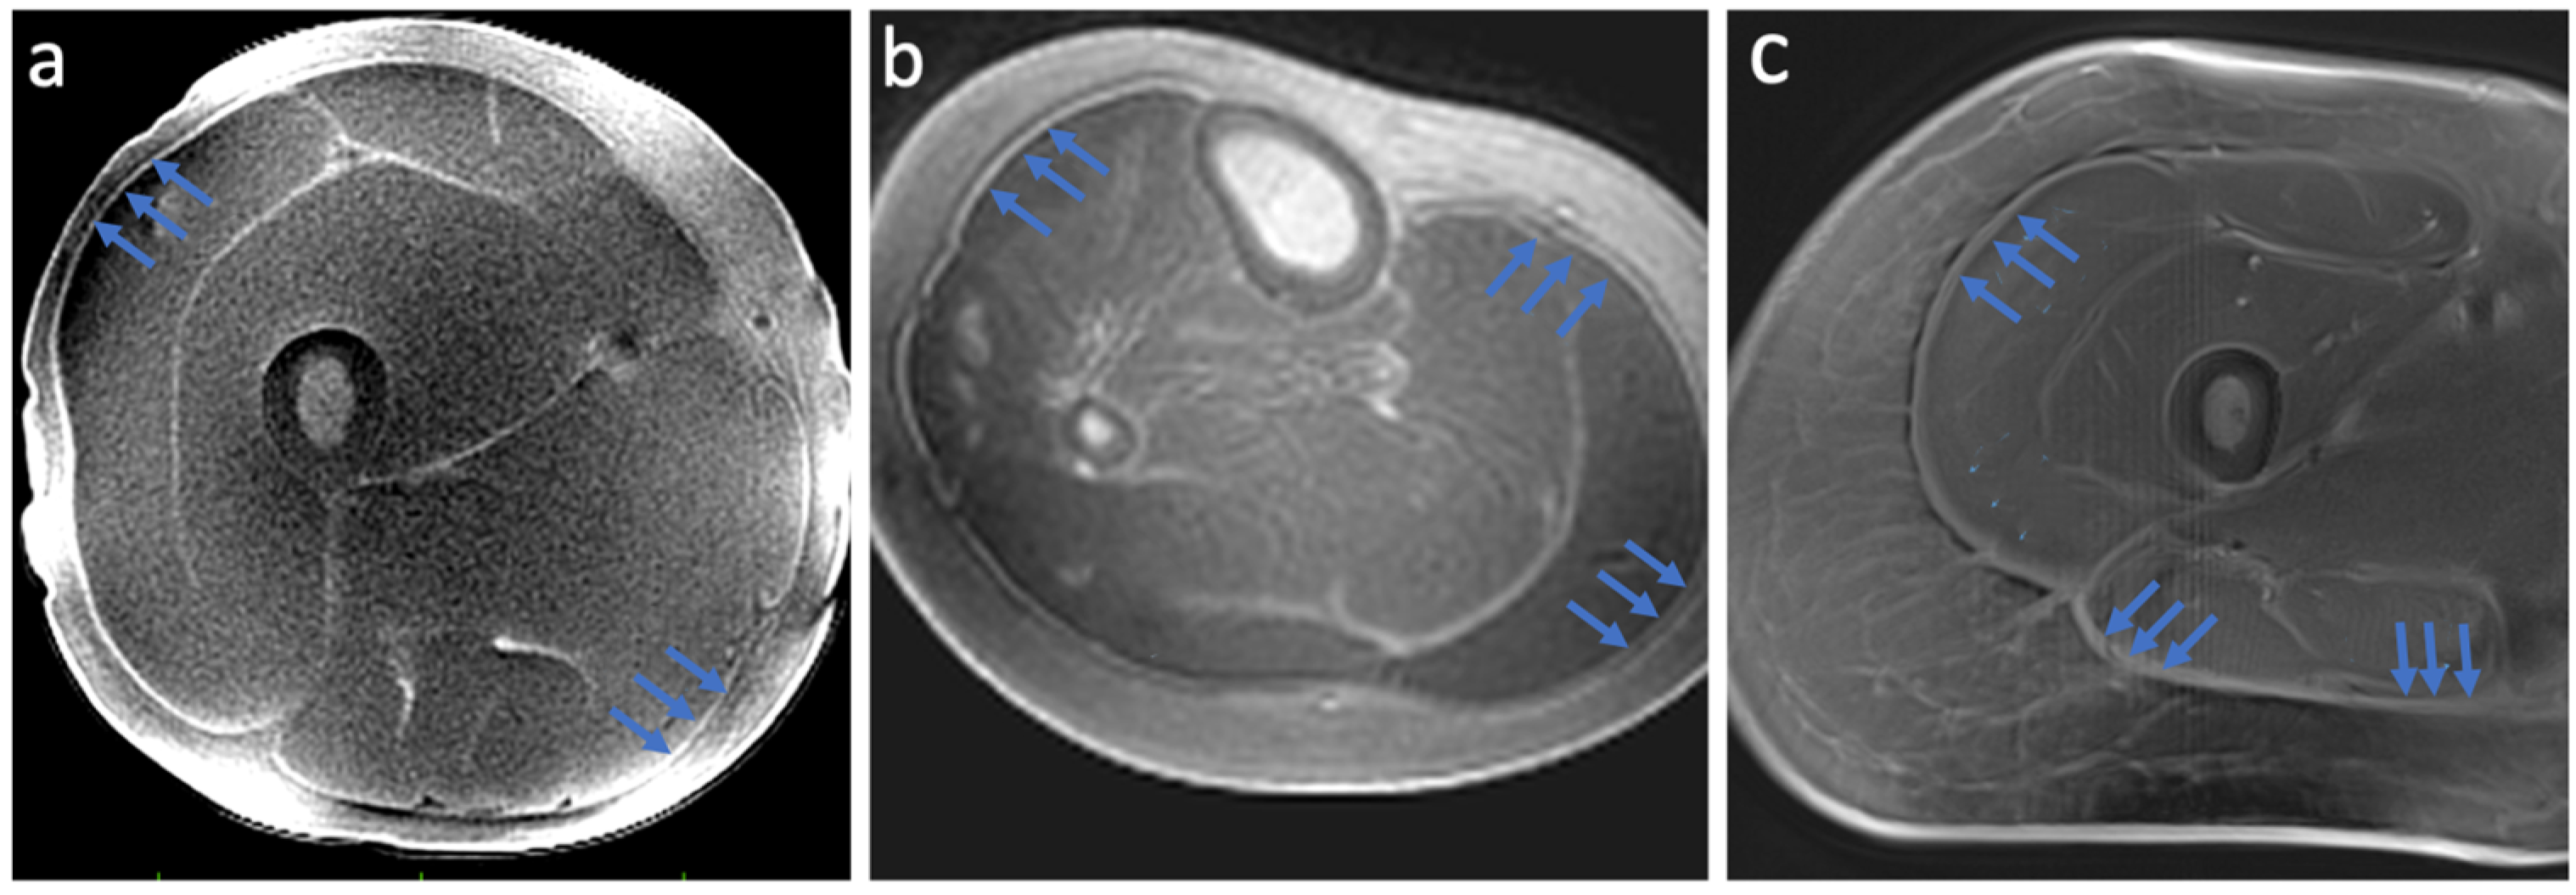

2.1. Optimized Ultra-Short Echo Time MRI

3.1. Ultra-Short TE Sequence Results